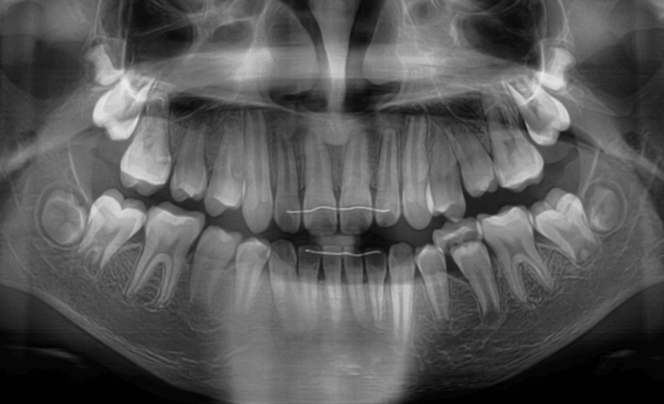

上歯前突+叢生症例 成長期

主訴 | 口元の突出感と歯並びが気になり、将来的な咬合状態を整える目的で来院された患者様です。 |

診断結果 | 11歳1か月の女性。骨格的には日本人標準に近く、歯性の上顎前突および叢生が認められました。上下顎ともに歯列のスペース不足があり、永久歯の萌出や歯列の整列に支障をきたす可能性があると診断されました。 |

治療内容 |

|

治療後の経過 | 動的治療終了後は、上下顎の歯列が整い、口元の突出感と叢生が改善されました。審美的・機能的なバランスが取れた状態となり、現在は取り外し式リテーナーを使用し、保定期間に移行しています。 |

治療期間 | 動的治療期間:2年6か月 通院回数:25回 |

治療費用 | 720,000円 |